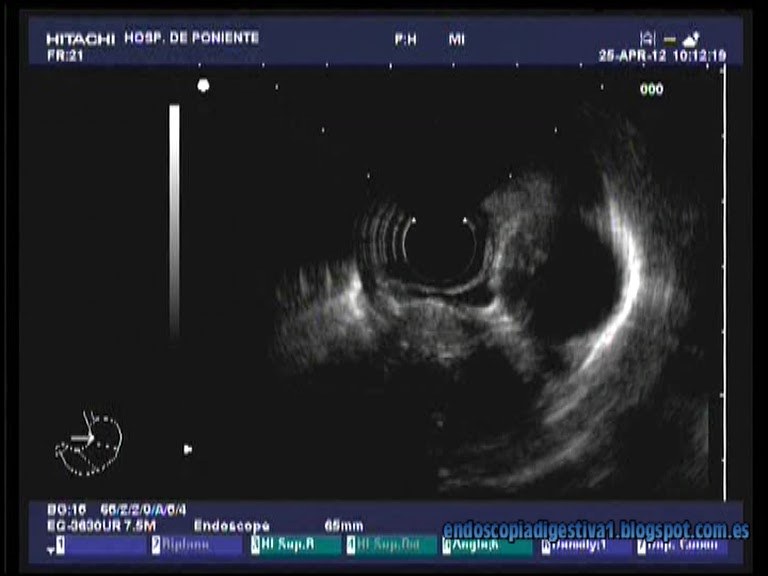

Paciente varón de 35 años de edad sin antecedentes de interés al que se le realiza una gastroscopia por síntomas moderados a severos de ERGE. En dicha exploración se aprecia una esofagitis de intensidad moderada así como una lesión de aproximadamente 1.5 cm de coloración amarillenta con mucosa de aspecto normal, dura al tacto del fórceps de biopsia en el esófago medio-distal (a unos 30 cm de la arcada dentaria). La histología de las biopsias realizadas (biopsia sobre biopsia) revelaron el diagnóstico de tumor de células granulares (tumor de Abrikossoff). Con idea de realizar una mucosectomía con bandas elásticas (técnica Duette) se realizó una ecoendoscopia radial que mostró una lesión homogénea, redondeada de 1.2 cm en esófago medio-distal hiperecogénica y bien delimitada, perteneciente a la 3ª capa esofágica (submucosa). Finalmente se realizó la mucosectomía sin complicaciones inmediatas, resecando en bloque la lesión. El estudio histológico confirmó el diagnóstico inicial y la resección completa de la lesión.

Los tumores de células granulares (tumor de Abrikossoff) son relativamente infrecuentes que se suelen localizar normalmente en la orofaringe, la piel y el tejido celular subcutáneo. En un 8-18 % de los casos se encuentra en el tubo digestivo, siendo el esófago la localización mas común (33 %). El 68 % de todos los tumores esofágicos se encuentran en esófago distal. Se cree que derivan de las células de Schwann. Generalmente son asintomáticos, aunque en ocasiones pueden sangrar o provocar disfagia y por ello se suelen diagnosticar de forma fortuita al realizar una gastroscopia por otros motivos. La mayoría de los tumores de células granulares son benignos, pero se han descrito casos de degeneración maligna en 1-3 % de los casos. Endoscópicamente se caracterizan por ser lesiones menores de 2 cm, en esófago distal, de coloración amarillenta con mucosa normal y de consistencia firme a la toma de biopsias. En la USE se caracteriza por ser de localización submucosa (2ª-3ª capa), bien delimitados e hiperecogénicos, que se suelen confundir por lo dicho con los lipomas. Se suele recomendar la realización de una PAAF por este motivo. Histológicamente se cracaterizan por ser postivos a S-100 con técnicas de inmunohistoquímica. Por la posible degeneración, se recomienda la resección endoscópica, siendo la mas usada la mucosectomía.